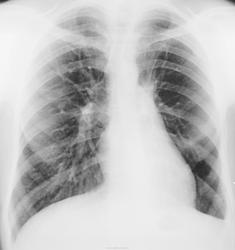

Справа в  S2 очаговая тень, в левом лёгком просветление средней зоны с обеднением лёгочного рисунка.

похоже на локальную эмфизему. может буллы левого легкого.

На гипоплазию одной из ветвей легочной артерии слева не похоже?

Нужна боковая. Корень легкого смещен кверху. Такая картинка может быть при нарушении бронхиальной проходимости (ателектаз в/доли или ее части при вздутии н/доли)..

А очень похоже. Насчет ателектаза сомневаюсь, купол диафрагмы на своем месте, а деформация корня может быть связана с гипоплазией.

О таком развитии только читал, возможно это и есть гипоплазия. Насчёт ателектаза сомневаюсь, ведь он чаще даёт типичную картину.

Возраст? В динамике отчетливое разрежение с/рисунка слева в среднем л/поле, сгущение(?) в верхних (парамедиастинальных) отделах, смещение корня кверху. Резко выраженная митрализация сердечной тени. Если это не ТЭЛА (при отсутствии клиники!), то в первую очередь, с моей точки зрения, нужно исключать центральный обЪемный процесс. Нужна боковая и, по-хоршему, исходя из ее данных ТМГ.

19 лет, клиники никакой.

Обеднение рисунка было и раньше. Огромное буллезное поражение или все-таки гипоплазия.